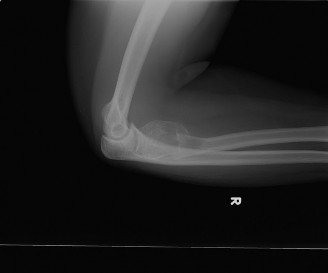

A 20-year-old female presents to the office complaining of pain and swelling in the elbow. She denies any rec…